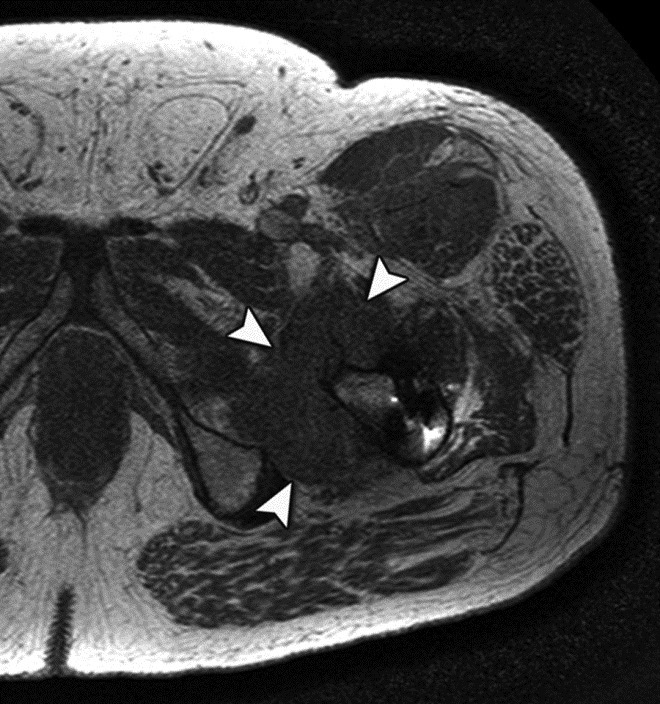

Adverse reaction to metal debris with anterior pseudotumor. Axial T1-weighted MR image shows large soft tissue mass (arrowheads) centered at the level of the lesser trochanter with involvement of the iliopsoas attachment site in a patient with metal-on-metal hip arthroplasty. Also note infiltrative involvement of the rectus femoris muscle.